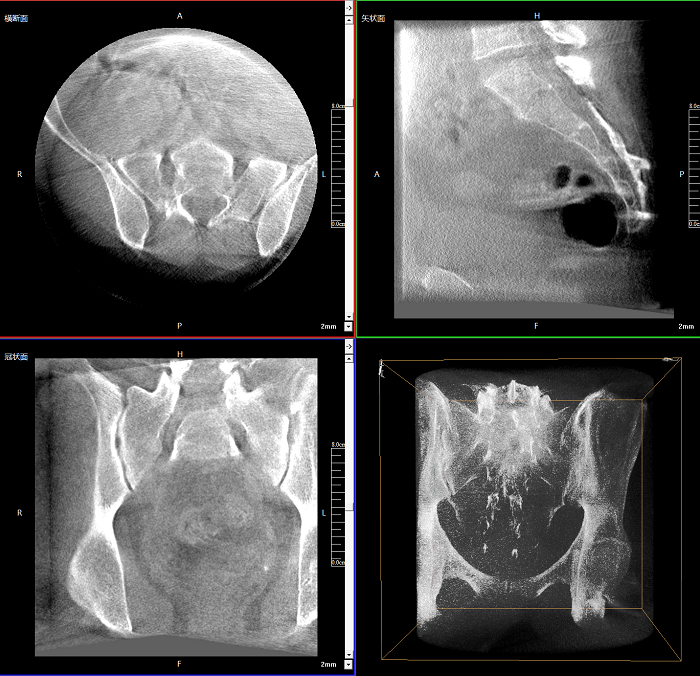

三維成像 全面觀察

任意視角、任意切面觀察

術(shù)中實(shí)時(shí)生成橫斷面、矢狀面、冠狀面及三維影像,可在任意切面、任意角度評估植入物和解剖結(jié)構(gòu)的相對位置。

術(shù)中CT檢查 減少翻修概率

通過術(shù)中三維影像的檢查,可以立即發(fā)現(xiàn)植入物的錯(cuò)位,減少不必要的第二次手術(shù),減少并發(fā)癥概率以及感染風(fēng)險(xiǎn)。

Clinical picture

臨床圖片